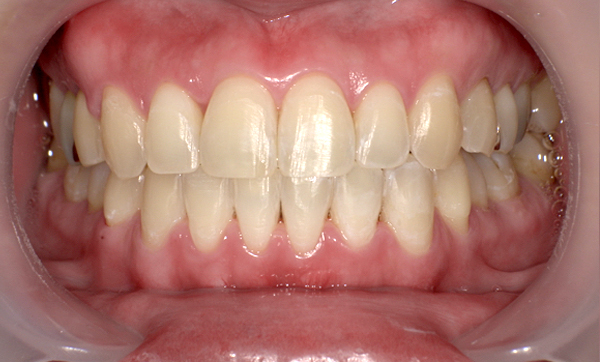

症例_009 「上下の前歯」症例

治療期間:7ヶ月金額:54万円+税20代女性捻転歯一部の反対咬合前歯のガタガタ

Before | After |